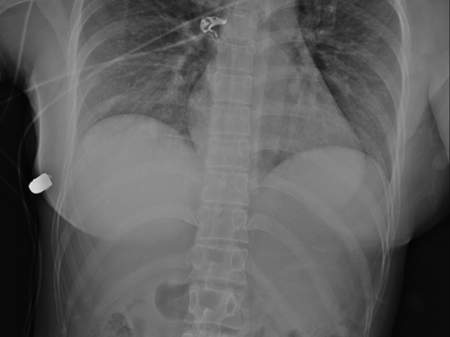

Scans of the woman’s chest show that the bullet entered her left breast first, before being deflected by the implant and entering her right breast, where the implant was found in a “completely flipped position.”

“Based on trajectory of bullet entry clinically and evaluation radiologically, the only source of bullet deflection… is the left breast implant,” the study reads.

“This implant overlies the heart and intrathoracic cavity and therefore likely saved the women’s life,” wrote the doctors.